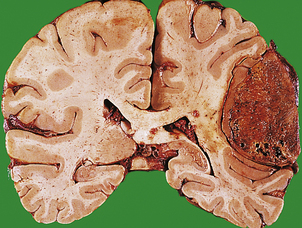

Herniations occur at several characteristic sites within the cranial cavity, depending on the site of the space-occupying lesion (Fig. 26.5). Transtentorial herniation is frequently fatal because of secondary haemorrhage into the brainstem (Fig. 26.6). This is a common mode of death in patients with large intrinsic neoplasms or intracranial haemorrhage.

image

Fig. 26.5 Sites of intracranial herniation. Space-occupying lesions in the cerebral hemispheres may cause herniation of the cingulate gyrus under the falx cerebri (1) or of the hippocampal uncus and parahippocampal gyrus over the tentorium cerebelli (2). Cerebellar tonsillar herniation through the foramen magnum (3) can occur with lesions in the cerebrum or cerebellum. A swollen brain will herniate through any defect in the dura and skull (4).

Fig. 26.6 Herniation effects in the brain. image A large haemorrhagic neoplasm (glioblastoma) is present in the right cerebral hemisphere, causing shift of the midline structures to the left and compression of the right lateral ventricle. image Transtentorial herniation at the base of the brain. A prominent groove surrounds the displaced parahippocampal gyrus (arrow). The adjacent 3rd nerve (N) is compressed and distorted and the ipsilateral cerebral peduncle (P) is distorted with small areas of haemorrhage.